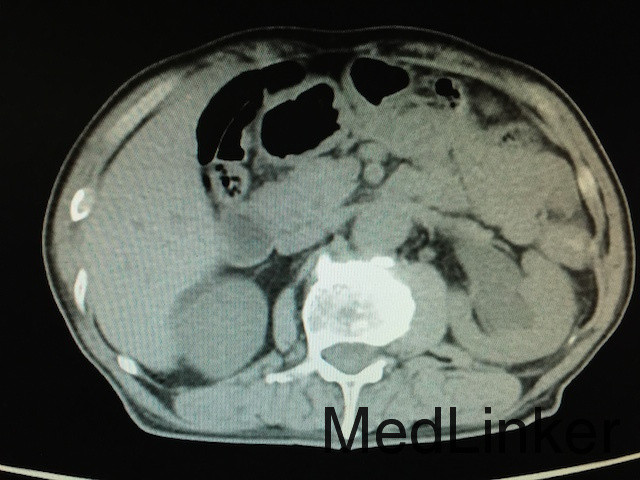

查体:无明显异常。 辅助检查:泌尿系CT(如下图所示):膀胱实性占位,增强扫描肿物呈不均匀强化,双侧输尿管及肾盂积水,结合患者既往史,考虑膀胱恶性肿瘤复发;骨扫描未提示骨转移灶;胸片无明显异常。

诊断:膀胱恶性肿瘤复发、双肾积水、膀胱憩室 治疗:建议行膀胱癌根治术+尿路转流术,患者家属拒绝,故行膀胱镜探查及双侧输尿管支架植入术改善双肾积水,改善肾功能。